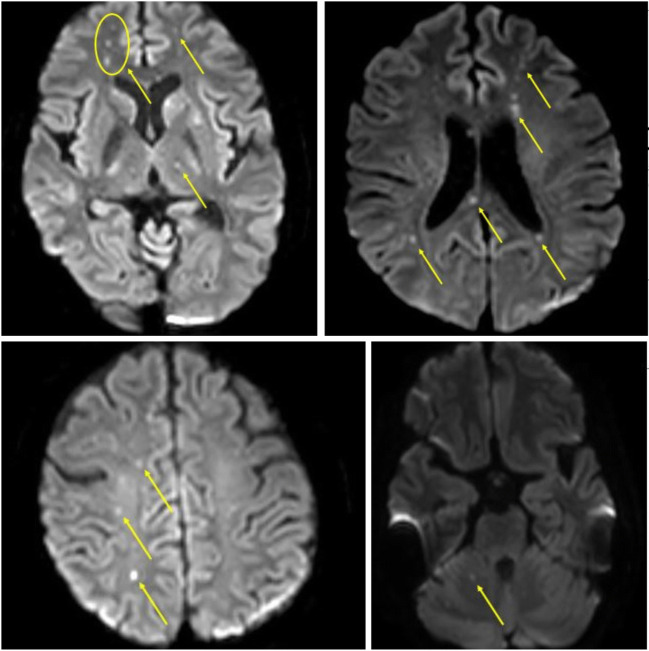

Fig. 1.

Diffusion-weighted magnetic resonance imaging (DW-MRI) of the brain showing extensive multifocal cerebral and cerebellar infarcts (yellow arrows)

A 49-year-old lady, with rheumatoid arthritis and type 2 diabetes mellitus, was diagnosed with rheumatic heart disease, severe mitral regurgitation, moderate aortic regurgitation, moderate tricuspid regurgitation, and a left ventricular ejection fraction of 40%. She was in atrial fibrillation with no intracardiac thrombus. She underwent aortic valve replacement with a 21-mm St. Jude Medical® mechanical valve (St. Jude Medical Inc., Minneapolis, MN), mitral valve repair with a 34-mm Carpentier-Edwards Physio II (Edwards Lifesciences, Irvine, CA, USA) annuloplasty ring, and tricuspid valve repair with a 32-mm MC3 (Edwards Lifesciences, LLC, Irvine, CA, USA) annuloplasty ring. On table evaluation revealed thickened, non-calcific aortic and mitral valve leaflets with fused commissures suggestive of rheumatic etiology. Following aortic cross-clamp release, there was bleeding from the aortic suture line posteriorly which could not be controlled with pledgetted polypropylene sutures from outside. The posterior tear was probably due to extension of the aortotomy incision while placing the mechanical aortic valve. The aorta was re-clamped, aortotomy was opened, and the posterior tear was repaired from the inside of the aorta with continuous running 5-0 polypropylene sutures. The aortotomy was closed and the cross-clamp was released. There was minimal persistent bleeding from the posterior aorta. BioGlue was applied as a film over the posterior aortic suture line and the transverse sinus was packed with oxidized cellulose polymer. Bleeding was controlled successfully and the patient was weaned off cardiopulmonary bypass. Intraoperative transesophageal echocardiography (TEE) was satisfactory. The patient was unresponsive for 48 h. Magnetic resonance imaging (MRI) with angiography (MRA) of the brain revealed multiple punctate scattered foci of acute infarcts in the bilateral frontal lobe, parietal lobe, centrum semiovale, right occipital lobe, frontal periventricular region, bilateral caudate nuclei, left lentiform nucleus, left thalamus, and splenium of the corpus callosum suggestive of an embolic shower (Fig. 1). Considering the infarct extent and her immediate postoperative status, she was not a candidate for neuro-intervention. A computed tomography (CT) of the brain repeated 72 h later revealed no interval increase in the infarct extent. She remained comatose and was tracheostomized on the seventh postoperative day. She regained consciousness on the fifteenth postoperative day. Repeat MRI done a month later revealed no interval change. With intense neuro-rehabilitation and physiotherapy over the following 6 weeks, she progressed remarkably and was weaned off the ventilator, and the tracheostomy was decannulated on the 59th postoperative day. She was discharged with no residual neurological deficits on the 61st postoperative day. She remained neurologically normal at her 6-month follow-up.